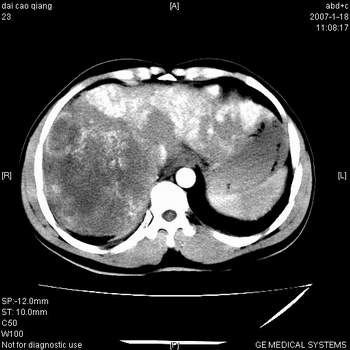

符合巨块型肝癌表现:

1、平扫低密度,增强后表现为快进快出。

2、动脉期可见迂曲的动脉供血血管

3、并可见门静脉右支癌栓形成

4、可见假包膜

5、腹主动脉旁结节影,考虑肿大淋巴结。

肝右叶巨大不均匀低密度肿块,前缘有假包膜,增强明显的呈快进快出表现,门脉右支有癌栓,病人虽然年轻但还是首先考虑肝右叶巨块形肝癌,病人血象高只能说有合并感染。不支持肝脓肿。